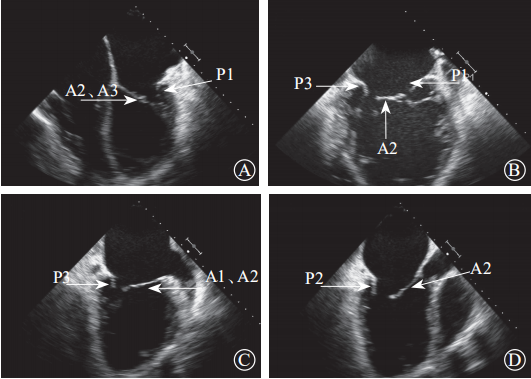

超声心动图在MR介入术中起着不可或缺的作用,下面以目前最为成熟的经导管二尖瓣夹合术MitralClip为例,阐述MR介入术中的超声评价。MitralClip是在经食管超声心动图实时监测和引导下的操作,所有的导管操作由经食管超声心动图监测和引导[17]。经食超声心动图首先引导房间隔穿刺,使得房间隔穿刺点距二尖瓣瓣环平面的高度为3.5~4.0 cm(图12)。之后,经食管超声心动图引导输送系统进入左心房并调弯、顶端垂直指向二尖瓣口。接着,经食管超声心动图引导夹合器在二尖瓣上方定位、夹合器进入左心室、引导夹合器捕获和夹合瓣膜。夹合器捕获瓣膜位置,应该位于彩色多普勒显示反流束最大处。在整个手术过程中,两个超声视野非常重要,为手术的工作切面,其中X-plane双切面,包括三腔心切面(左心室长轴切面)及二尖瓣交界处二腔心切面(图13)。三腔心切面可以显示二尖瓣A2、P2的位置,捕获瓣膜前二尖瓣夹合器应该在这个切面显示为V字形,此时瓣夹合器臂与二尖瓣开放线垂直,分别位于A2、P2的位置,在该切面通过调整夹合器位置可使得夹合器更靠近前叶或后叶;二尖瓣交界处二腔心切面显示P1、A2、P3,捕获瓣膜前二尖瓣夹合器在该平面应该为直线形,在该切面通过调整夹合器位置可使得夹合器更靠近瓣环内交界(P3或A3)或外交界(P1或A1)。另外一个工作切面为三维超声心动图的“二尖瓣外科视野”,可以整体观察夹合器的位置、臂指向的方向(图14)。目前有限经验显示,经心尖二尖瓣夹合术(ValveClamp)术中超声心动图指导和MitralClip总体上类似,但仍有部分差异,其超声心动图规范尚在探索中。

注:LA,左心房;LV,左心室

图13 经食管X-plane双切面显示夹合器与二尖瓣前后叶垂直(箭头所示)A. 二尖瓣交界处二腔心切面,显示夹合器为直线形;B. 左心室长轴切面,显示夹合器为“V”字形